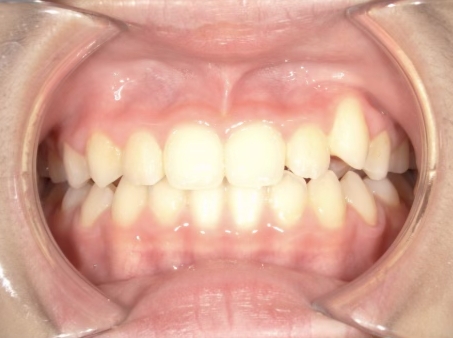

治療中⑨ 中3:14y4m

モノブロック装置で左上八重歯が改善しました

今後、必要によりマルチブラケット法へ移行予定です